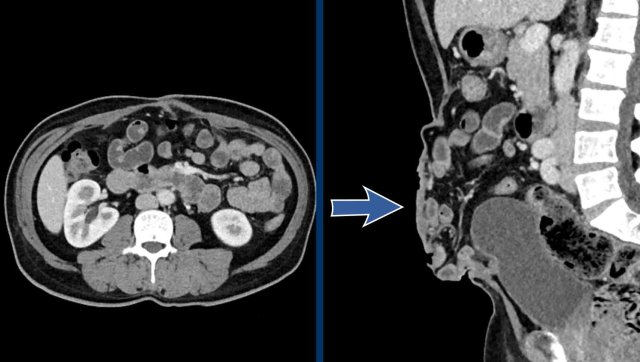

Image

In this patient the loss of domain is > 20% and additional strategies will be necessary to increase the abdominal capacity and compliance.

In this patient with a large hernia, the measurements are as follows:

• Hernia Sac Volume = (274 x 71 x 304 mm x 0,52) x 10-6 = 3.1 liter.

• Abdominal Cavity Volume  = (251 x 131 x 342 mm x 0,52) x 10-6 = 5.8 liter.

• Total Peritoneal Volume = ACV + HSV = 3.1 + 5.8   = 8.9 liter.

The loss of domain in this case is the volume of the hernia sac divided by the volume of the total peritoneal cavity:

3.1: 8.9 = 35%.

This is far greater than 20% and means that there is a high risk of complications during and after a simple abdominal wall repair.